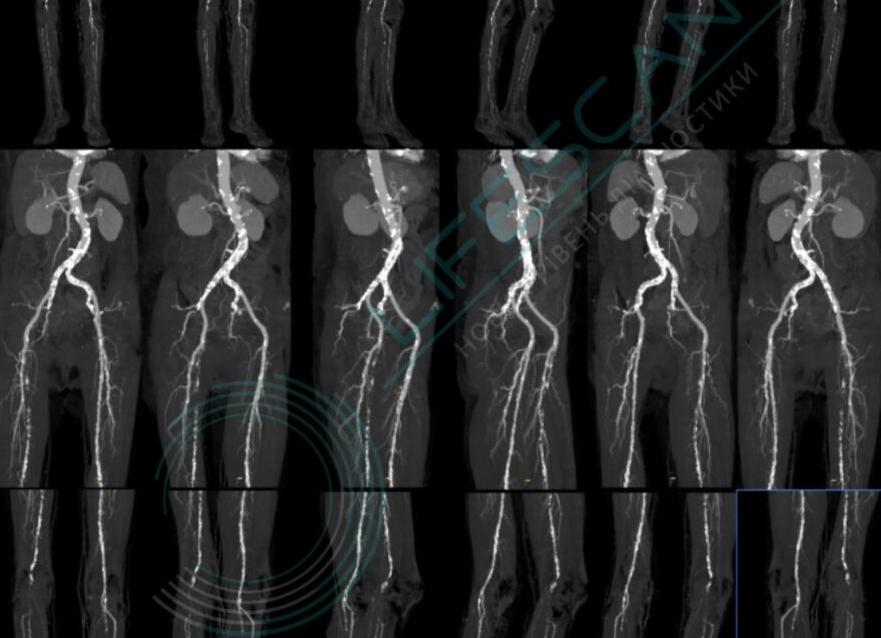

КТ ангиография сосудов нижних конечностей — это современный высокоинформативный малоинвазивный метод исследования. Он дает информацию о состоянии стенки и просвета сосуда, его анатомических особенностях. При исследовании отображаются артерии и вены с возможностью получения 3D-реконструкций.

Исследование может быть уточняющим после УЗИ сосудов нижней конечности. КТ ангиография сосудов нижних конечностей также применяется при определении количества коллатералей между поверхностными и глубокими венами, для выявления скрытых венозных тромбов при варикозе и др. Исследование всегда проводится с внутривенным контрастными усилением.